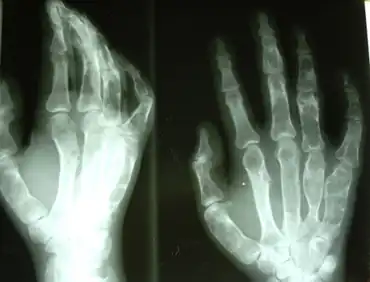

X-ray showing calcified enchondromas localized in finger a 37-year-old patient affected with Ollier disease